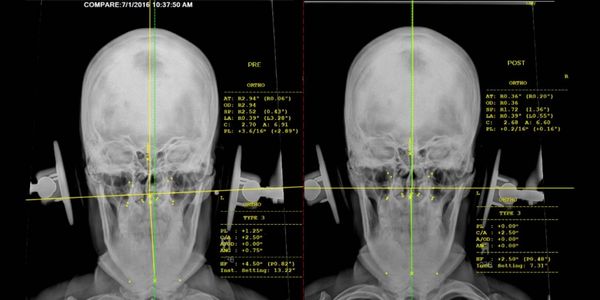

It’s called a Vertebral Subluxation. That is what we diagnose & correct. It's when the bones of the spine, specifically the first two bones of the spine the Atlas (C1) and Axis (C2), shift, twist or jerk out of normal or right position, producing a "kink". These bones get stuck and remain in that abnormal position in relation to the other bones immediately above or below it.

Due to the bio-mechanics of the spine this Subluxation causes compensatory misalignments all the way down the spine even to the pelvis and hip joints. Leading to what is called body imbalance. A lot of the structural issues such as, headaches, neck pain, mid to low back pain, shoulder pain, hip pain, knee pain and feet pain are caused by this body imbalance.

This body imbalance causes the weight of our head to be thrown off the center of gravity, causing brain imbalance. Our body tries to bring the head back to the center of gravity by causing the spine to shift, twist and cause muscles to contract all the way down the spine.